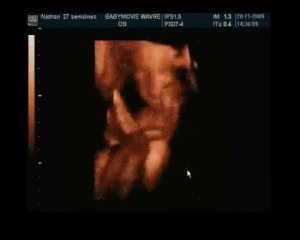

User: Mahmoud Soliman

Views: 13

Uploaded: 2015-09-09

Duration: 00:26